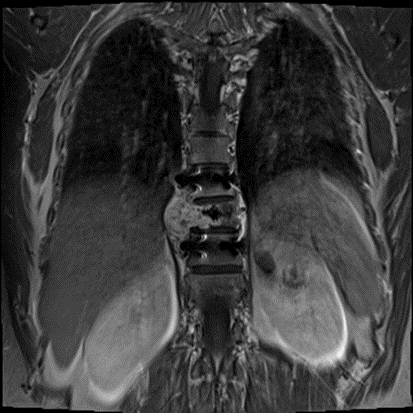

肿瘤累计3段胸椎 , 已明显压迫脊髓

在门诊接诊到患者卜女士时 , 她的下肢无力已经颇为严重 。 随后进行的影像检测又发现了许多不好的征兆:肿瘤累及3个胸椎、已经明显压迫脊髓、肿瘤体血供丰富……必须尽快手术解除压迫以抢救脊髓功能 。

鉴于卜女士上次手术的凶猛出血以及病理诊断仍不明确的情况 , 王晋教授立即召集了多学科讨论 。 影像科艾飞、张赟以及尹韶晗三位医生明确了影像学特征支持中间性或低度恶性肿瘤 。 由于肿瘤与硬脊膜关系密切 , 放疗科李巧巧副主任医师制定了术后的放疗计划 , 以最大限度地降低复发率 。